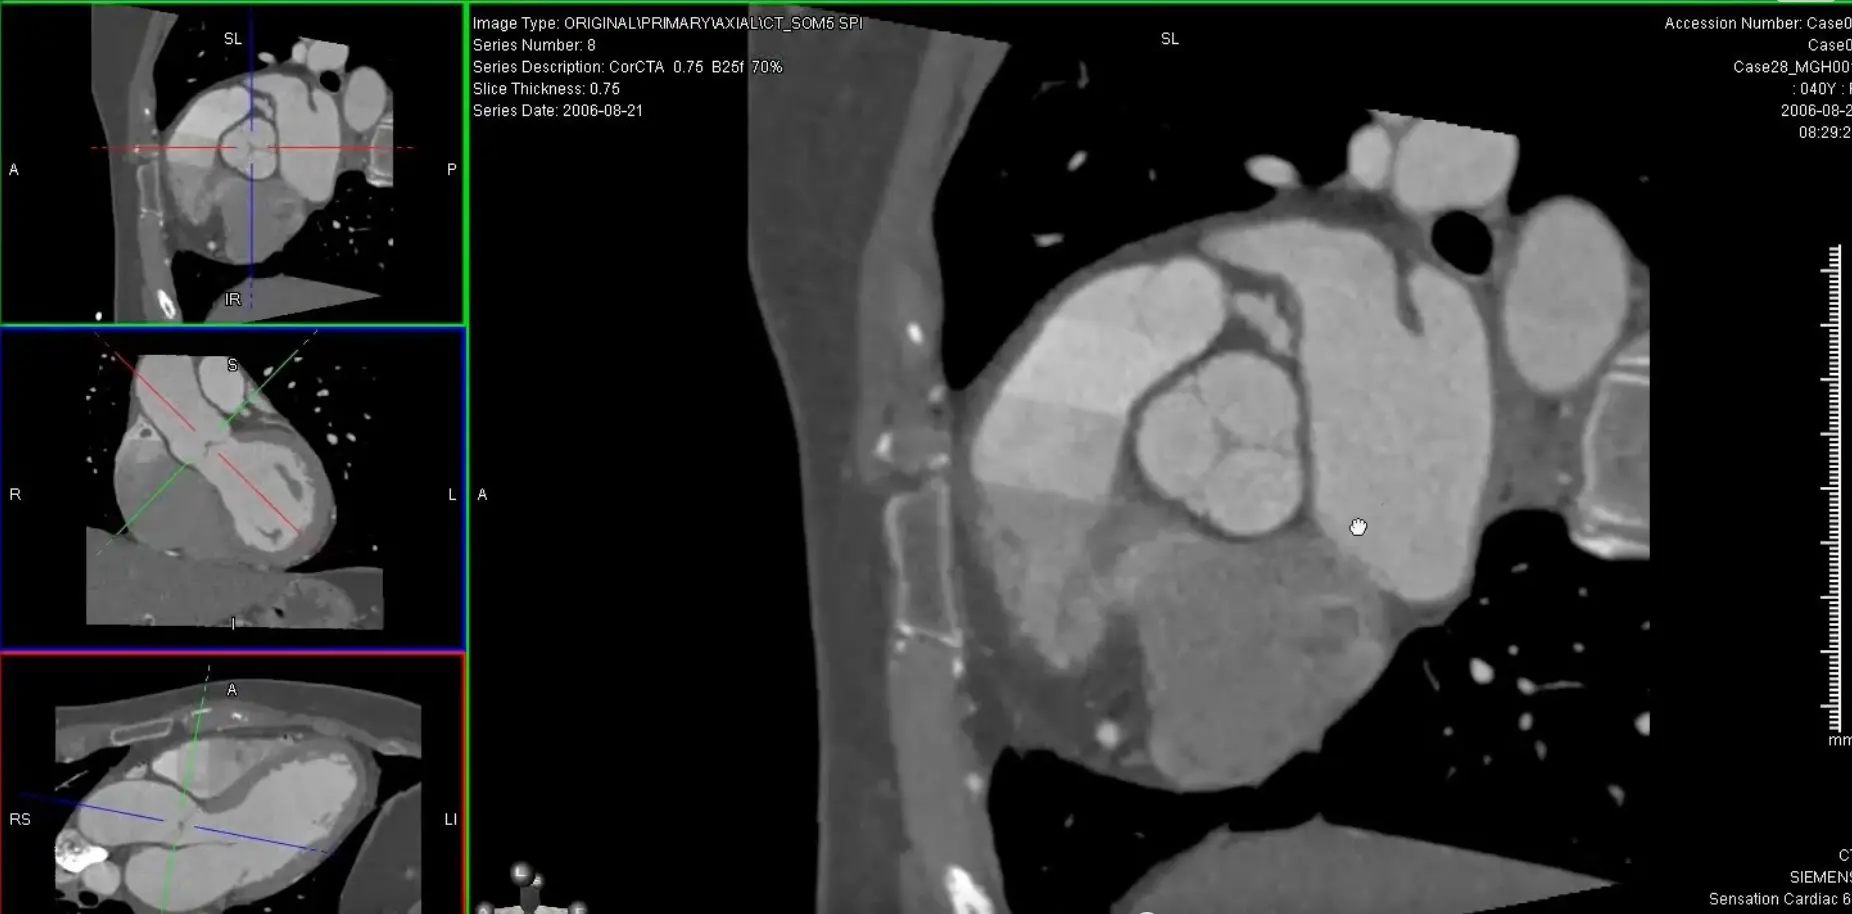

’C’ view of RCA

Useful to view RCA and LCx

Both the RCA and LCx lie along the atrioventricular groove, so the ‘C’ view is useful to evaluate the RCA and LCx. When you get your RCA lined up (as below) in the MIP projection, you can scroll along and assess the LCx as well.

- Coronal view: Position crosshair (⌖) at mid-RCA

- Axial view: center on the SAX view of the RCA

- rotate ⌖ in the axial view until you are aligned parallel to the ventricular septum on your coronal window

- In your axial view, rotate ⌖ to align the orthogonal view (e.g. coronal window) so that the orthogonal view is along the atrioventricular groove

- Switch to MIP view

MPR of ‘C’ view of RCA

Above, but changed to MIP